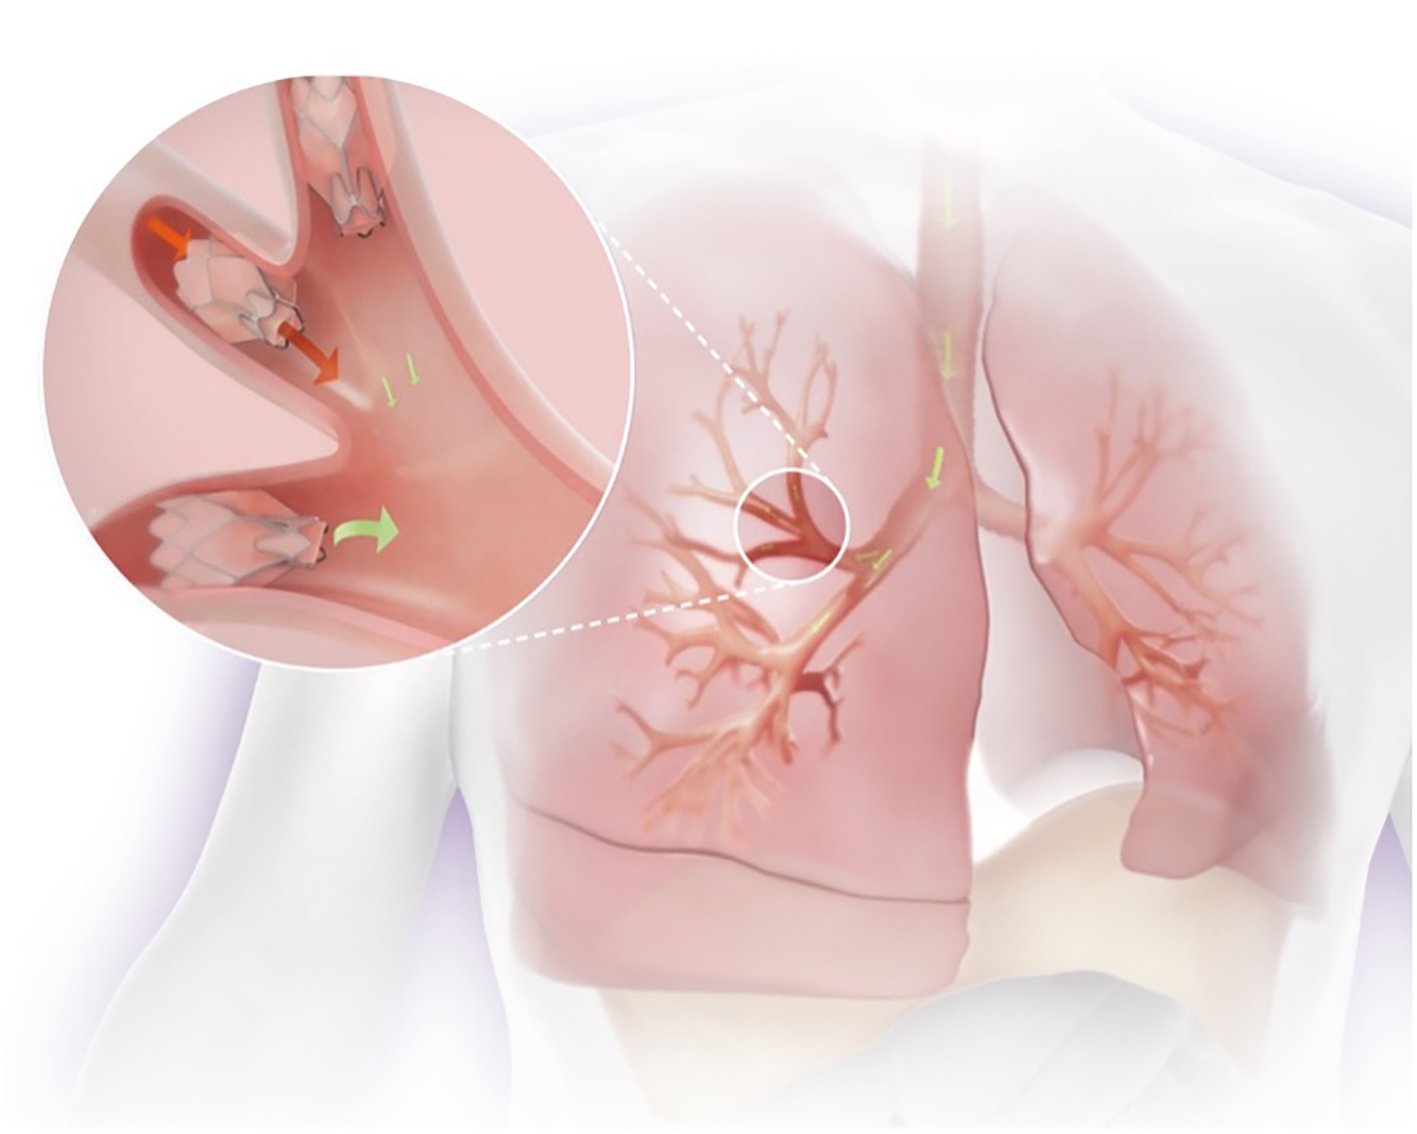

Patienter som lider av svår emfysemsjukdom upplever kronisk andnöd och har nedsatt ansträngningskapacitet och dålig hälsorelaterad livskvalitet. Trots optimal farmakologisk terapi, rökavvänjning och lungrehabilitering förblir majoriteten av patienterna betydligt nedsatta i funktionsnivå. Därför är behandlingen ofta inriktad på symtomlindring och sjukdomskont­roll [1]. Lungvolymreducerande kirurgi kan ge kliniska fördelar hos utvalda patienter med övervägande ovanlobssjukdom och låg funktionsnivå. Dessvärre är denna procedur förknippad med hög perioperativ sjuklighet och dödlighet [2]. Bronkoskopisk lungvolymreduktion är ett alternativ till lungvolymreducerande kirurgi för att minska lungornas hyperinflation. Vid bronkoskopisk lungvolymreduktion placeras enkelriktade ventiler i samtliga segment i en utvald kraftigt hyperinflaterad så kallad mållob (Figur 1). Efter behandlingen töms luften successivt ur loben genom de endobronkiella ventilerna, vilket resulterar i lungvolymreduktion och ofta fullständig atelektas av målloben (Figur 2). I Sverige har två analyser publi­cerats angående behandlingens evidensnivå (health technology assessment, HTA), 2013 och 2018 [3, 4]. Riise et al rapporterade i Läkartidningen 2018 om HTA-analysen som var baserad på 9 randomiserade kontrollerade studier [5-13] och drog slutsatsen att bronkoskopisk lungvolymreduktion med ventiler gav kliniskt betydelsefulla förbättringar i livskvalitet, fysisk prestationsförmåga och lungfunktion hos patienter med emfysem, men att allvarliga komplikationer i direkt anslutning till behandlingen var vanliga, i förs­ta hand pneumotorax [14]. Global Initiative for Chronic Obstructive Lung Disease (GOLD) har på senare år uppgraderat bevisnivån för endobronkiell ventilbehandling till den högs­ta nivån och rekommenderar användning av denna metod för patienter med kroniskt obstruktiv lungsjukdom (KOL) [15].

Figur 2. DT före och efter behandling av vänster underlob, som minskat i storlek efter behandlingen. Man kan också se intrabronkiella ventiler och en uppdragen diafragma på vänster sida som en effekt av behandlingen.